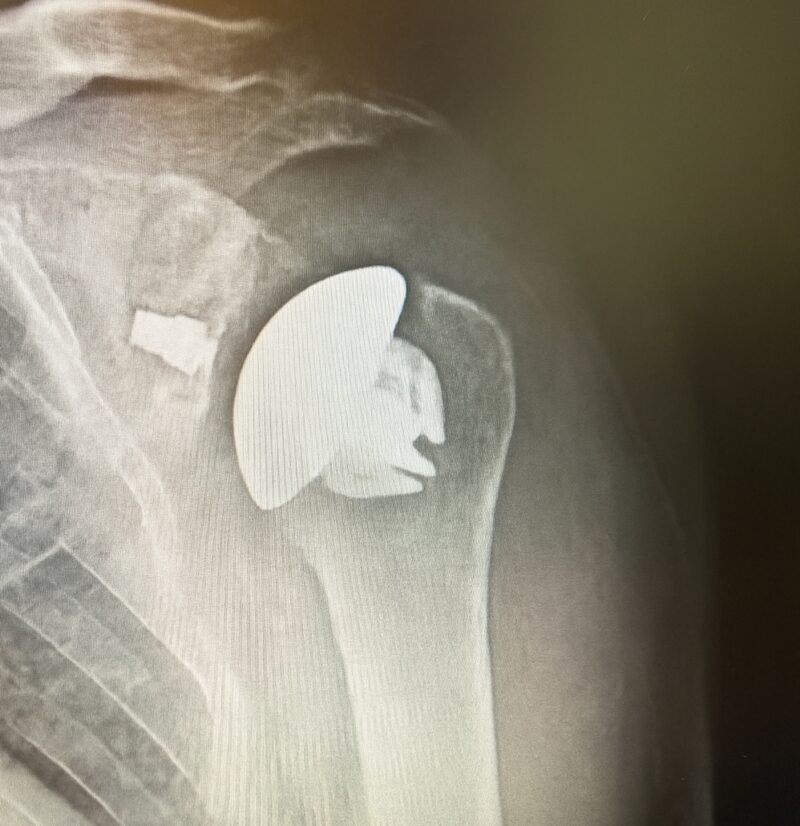

Summary The OsseoFit™ Stemless Shoulder System is indicated for anatomic total shoulder arthroplasty in patients where a bone-sparing, stemless solution is desired to maximize humeral fixation. It achieves this through OsseoTi® Porous Metal Technology and a site-specific fin design that creates a stable, biological press-fit while simplifying the surgical workflow with integrated suture holes. This system addresses a wide variety of patient anatomies using its versatile inlay and onlay size options. Indications Indications osteoarthritis indicated for anatomic total shoulder applications Contraindications local/systemic infection, sepsis, and osteomyelitis active local or systemic infection sepsis osteomyelitis inadequate humeral bone inadequate bone may lead to poor implant fixation large metaphyseal cysts may compromise stemless fixation irreparable cuff tear rotator cuff must be functionally reconstructable for anatomic total shoulder arthroplasty revision of any stemmed or stemless prothesis contraindicated for revision of any stemmed or stemless prosthesis Anatomy Osteology humeral head anatomic neck greater tuberosity lesser tuberosity bicipital groove metaphyseal cancellous bone Muscles deltoid forms the lateral border of the deltopectoral interval pectoralis major forms the medial border of the deltopectoral interval subscapularis released and repaired according to surgeon preference Ligaments glenohumeral capsule is released as needed to expose the humeral head and glenoid coracohumeral ligament contributes to rotator interval constraint superior, middle, and inferior glenohumeral ligaments contribute to anterior stability transverse humeral ligament overlies the bicipital groove Nerves axillary nerve courses inferior to the subscapularis and around the lateral humerus must be protected musculocutaneous nerve lies medial to the coracobrachialis and conjoint tendon suprascapular nerve is at risk with aggressive posterior-superior glenoid exposure Blood supply anterior and posterior humeral circumflex arteries arcuate artery is a terminal branch of the anterior humeral circumflex system suprascapular and circumflex scapular vessels Preoperative Planning X-rays A/P, scapular Y and axillary views evaluate bony anatomy, humeral head position, glenoid wear, deformity, and acquired bone loss use x-ray templates to estimate stemless humeral implant size assess whether an anatomic total shoulder reconstruction is appropriate CT assess bone quality and identify any humeral bone tissues use to assess bone quality and identify humeral bone issues that may affect implant selection evaluate metaphyseal bone stock, cysts, avascular necrosis, deformity, and cortical support Approach Extended deltopectoral anterior incision with an optional biceps tenodesis beginning immediately above the coracoid process and extending distally and laterally, following deltopectoral groove along the anterior border of the deltoid Technique Humeral head resection expose the humeral head and identify anatomic neck landmarks fixed-angle resection targets 135° inclination and 30° retroversion select left- or right-specific extramedullary resection guide align the guide post with the humeral shaft for fixed-angle resection align the 30° version rod with the forearm flexed at 90° place pins to define version and inclination and to stabilize the cutting surface resect the humeral head through the far side of the humeral head adjust the resection with the guide or calcar planer if needed assess bone quality with direct pressure perpendicular to the resected surface consider stemmed humeral fixation if cancellous bone is easily depressed or primary stability is questionable Humeral protection during glenoid preparation select the humeral resection cover that most closely fits the resected surface prepare the glenoid using the appropriate compatible glenoid technique remove the humeral resection cover before humeral sizing Humeral sizing place the humeral sizer onto the resection surface select the size intended to optimize cancellous bone fixation without violating the inner cortical rim orient the sizer so the bicipital groove bisects the superior and anterior fins insert the central Steinmann pin through the center of the sizer and through the lateral cortex avoid deep lateral cortical penetration to reduce risk to the axillary nerve place a lateral humeral retractor as needed to protect the axillary nerve confirm sizing after any additional planing Humeral bone preparation (boss reaming) ream until the boss reamer bottoms out on the resected surface ream over the central Steinmann pin with the boss reamer protect the lateral humerus and axillary nerve with a retractor remove the boss reamer while leaving the central Steinmann pin in place Humeral bone preparation (broaching) select the reference foot based on implant size select the broach that corresponds to the humeral sizer align the broach superior fin with the superior indicator line on the broach inserter slide the assembly over the central Steinmann pin until the broach contacts the resection surface remove the inserter-reference foot assembly and central Steinmann pin perform broach stability testing consider stemmed humeral fixation if the broach is unstable Humeral head trialing determine humeral head diameter and height using the humeral head sizing template or the resected humeral head seat the head trial assembly into the broach rotate the trial assembly with the hex driver to assess coverage of the resection surface confirm alignment with the anterior and posterior borders of the humeral resection increase offset if the head trial does not cover one side of the resection decrease offset if the head trial overhangs the resected bone reduce the joint and perform trial range of motion record the final offset letter or interval on the proximal humerus remove and disassemble the head trial assembly Implant insertion remove the broach with the slap hammer while maintaining an on-axis trajectory use the same reference foot size used for broach insertion select the implant size corresponding to the final broach and operative side slide the reference foot down until it uniformly contacts the resection surface confirm superior fin markings on reference foot, implant, and bone are aligned disengage the inserter-reference foot assembly with axial traction and slight rotational force as needed onlay implant center boss is slightly proud of the resection surface, with fin top surfaces flush inlay implant sits below the resection surface Humeral head implantation select the final humeral head implant matching the trial diameter and height use the offset letter or interval determined during trialing place the humeral head into the concave surface of the impactor base on a rigid sterile table impact the adapter into the humeral head with the disposable impactor using a mallet, strike the head impactor at least twice until the humeral head is flush with the resection visually confirm uniform seating consider implant subsidence and stemmed fixation if no pre-impaction gap is present Technical specifications Implant design anatomically shaped asymmetric anchor design designed to match natural asymmetric humeral anatomy designed to maximize cancellous bone fit and help avoid cortical impingement six-fin configuration with progressive tapered wedge design fins are designed for press-fit insertion each fin contains a fully porous window anterior suture holes are present for subscapularis repair Porous technology OsseoTi® Porous Metal Technology is used in the stemless implant porous architecture is designed to mimic human cancellous bone design incorporates a fully porous 3D printed OsseoTi® lattice within a titanium framework Technical specifications OsseoFit Onlay Anchor Implant Side Size Left 1, 2, 3, 4, 5 Right 1, 2, 3, 4, 5 OsseoFit Inlay Anchor Implant Side Size Left 1, 2, 3, 4, 5 Right 1, 2, 3, 4, 5 OsseoFit Humeral Head Adapter